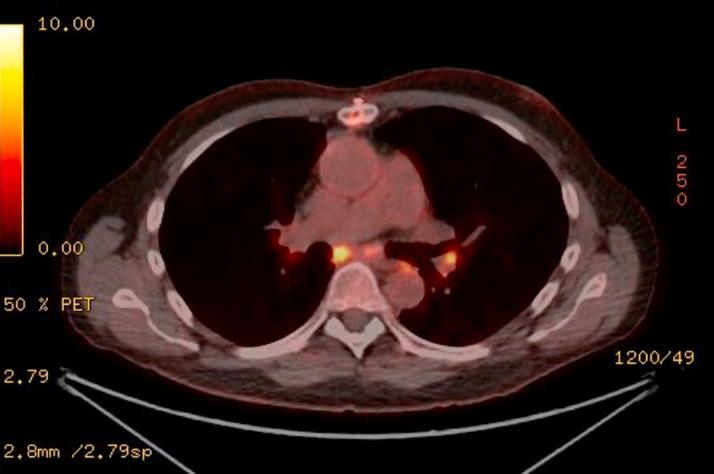

Giant cell myocarditis (GCM) and cardiac sarcoidosis share clinical and histologic features, but whether they represent separate processes or lie on an inflammatory cardiomyopathy spectrum is unclear. We present a case of cardiogenic shock thought to be secondary to biopsy-proven GCM with a subsequent post-transplant diagnosis of sarcoidosis through 18-fluorodeoxyglucose positron emission tomography and biopsy.

巨细胞性心肌炎(GCM)与心脏结节病具有共同的临床和组织学特征,但它们是代表不同的疾病过程还是属于炎症性心肌病谱系尚不清楚。我们报告一例心源性休克病例,最初认为是活检证实的GCM所致,随后通过18氟脱氧葡萄糖正电子发射断层扫描和活检在移植后诊断为结节病。